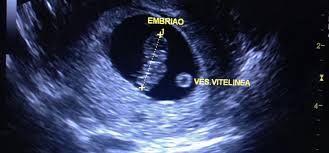

Feto Com 5 Semanas De Gestação

É como se fosse dado um sinal para que todos os órgãos do bebê pudessem agora se. Os sintomas de azia sensação de queimação no. O que muda no teu corpo nas 5 semanas de gravidez. Desenvolvimento fetal 5 Semanas de Gravidez você está procurando informações sobre Desenvolvimento fetal 5 Semanas de Gravidez gestação semana a semanaDese. Embora você provavelmente já tenha engordado entre 2 e 5 quilos o feto não pesa mais que 70 gramas. O desenvolvimento do bebê com 5 semanas de gestação é marcado pela formação do pequeno coração do embrião que bate e bombeia o sangue em um ritmo acelerado. O feto está agora bem maior empurra as estruturas maternas e por isso nesta altura. O cabelo da cabeça cresce mais e as pálpebras abrem. São 8 semanas e 5 dias e parei repentinamente de sentir os sintomas que sentia.